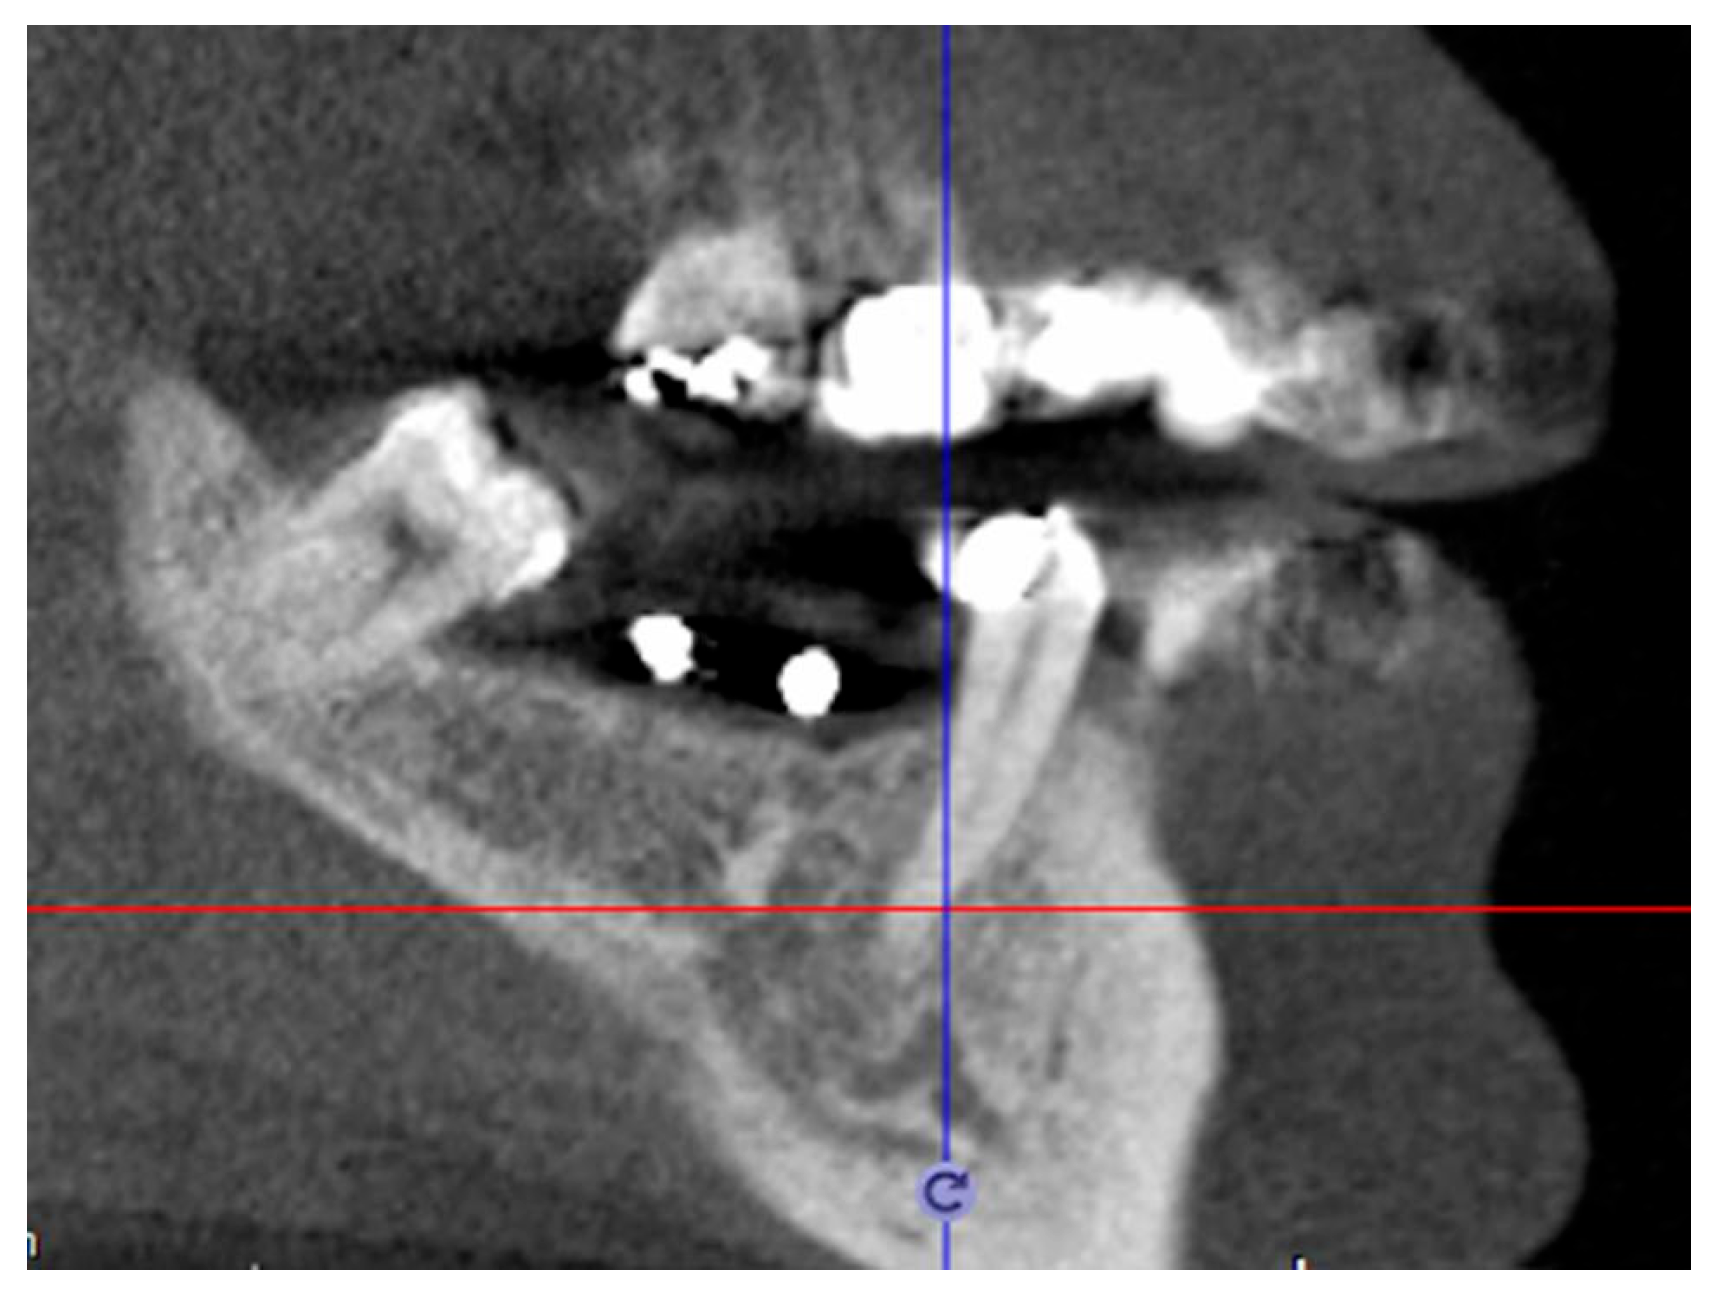

|

CBCT taken with template | Definitive patient selection Elegibility criteria: fixture position confirmed by CBCT |

Identification implant sites on the mucosa |

Check identification accuracy by template |